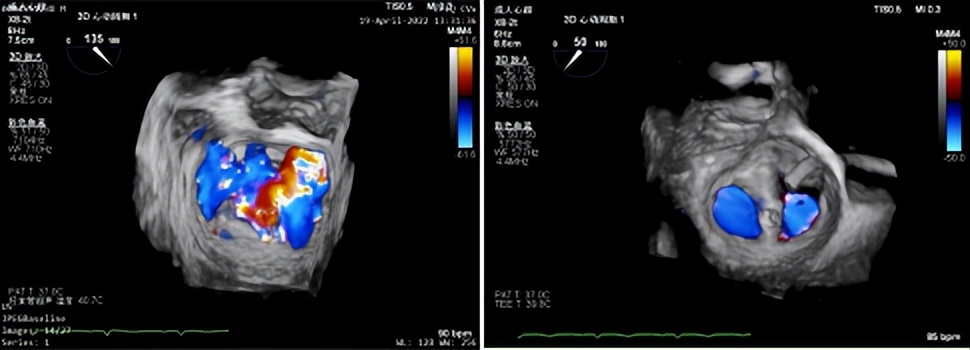

图三(3D示后叶脱垂伴重度关闭不全)

食道超声显示术后即刻效果显著,心房侧未见返流信号(图九),3D显示二尖瓣呈组织桥形态良好的双孔状,返流消失(图十),临床症状明显改善,术后效果堪称完美。

图十(左:术前食道3D示4+大量返流;右:术后二尖瓣呈组织桥形态良好的双孔状,返流消失)